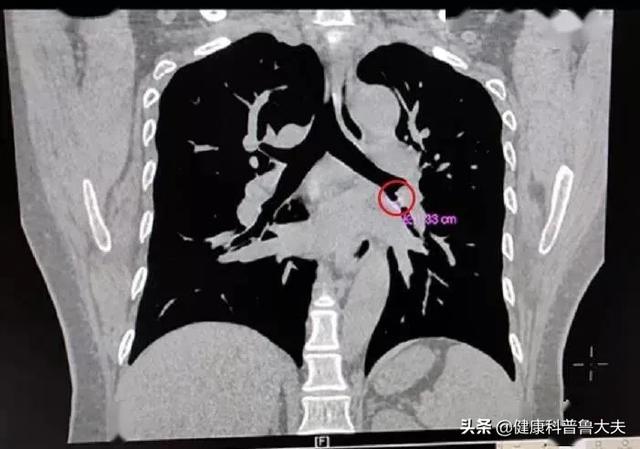

まず、最近咳がひどい人は、呼吸器科に行くことをお勧めします。例えば、肺腫瘍があるかどうか、変則的な咳があるかどうか、その他の病気の原因などです。どのようにチェックするかについては、患者の具体的な状況に応じて、胸部CTや肺機能などの検査を行うかどうかを決定します。総合的に判断すると、咳が非常に強い場合は、まず呼吸器科に行って呼吸器疾患をチェックするのが適切かつ合理的です。

まず、咳の原因を調べる必要があります。例えば、上気道感染症、気管支炎、肺炎など、咳や痰が出やすい場合は、病院で定期的に血液検査を行い、CRP、カルシトニノーゲンなどを調べ、同時に肺のCTを撮ります。ウイルス感染によるものであれば、抗ウイルス薬を同時に使用することもできますが、医師の指導のもとで使用する必要があります。咳がより深刻な場合は、ネブライザー吸入療法を行うこともできます。ネブライザー吸入は皮膚や粘膜に直接吸収され、咽頭炎による炎症、乾いた咳に効果があり、非常に優れています。もし痰が多ければ,またいくつかの経口アミノブロミン内服液の治療効果を服用することができて,すぐに咳を和らげることができます。